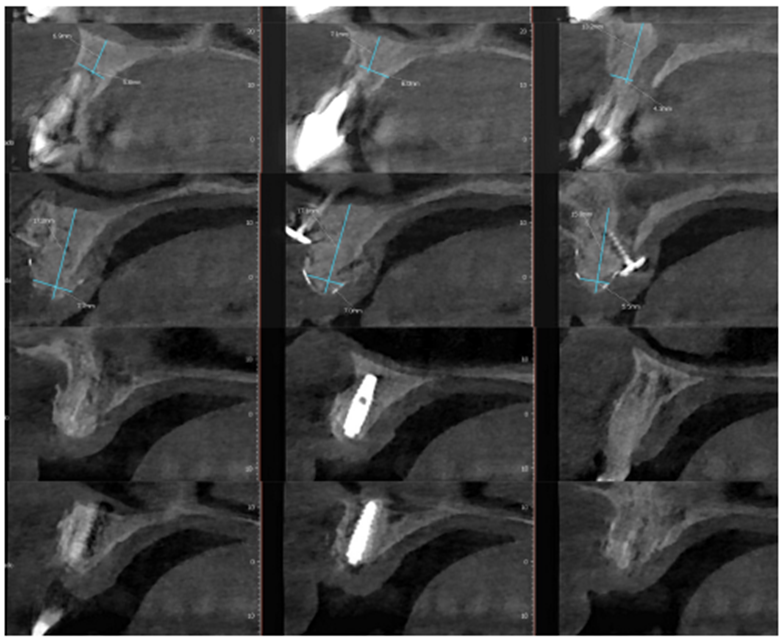

Após oito meses, foi realizada nova tomografia para análise do ganho ósseo vertical, assim como o planejamento dos implantes do tipo Cone Morse Maestro – Implacil De Bortoli (Figura 7). Foram planejados e realizados dois implantes 3.5 X 11 mm Cone Morse Maestro após remoção da membrana Cytoplast, devido ao ótimo ganho ósseo vertical, evidenciando sucesso da técnica de regeneração óssea guiada (Figuras 8, 9 e 10). Após a espera de apenas três meses devido a qualidade do implante e suas câmaras de cicatrização, o que possibilita uma osseointegração precoce, foram realizadas duas metalocerâmicas parafusadas sobre pilares Ideale reto, da Implacil De Bortoli, devido ao ótimo posicionamento tridimensional (Figuras 11 e 12).